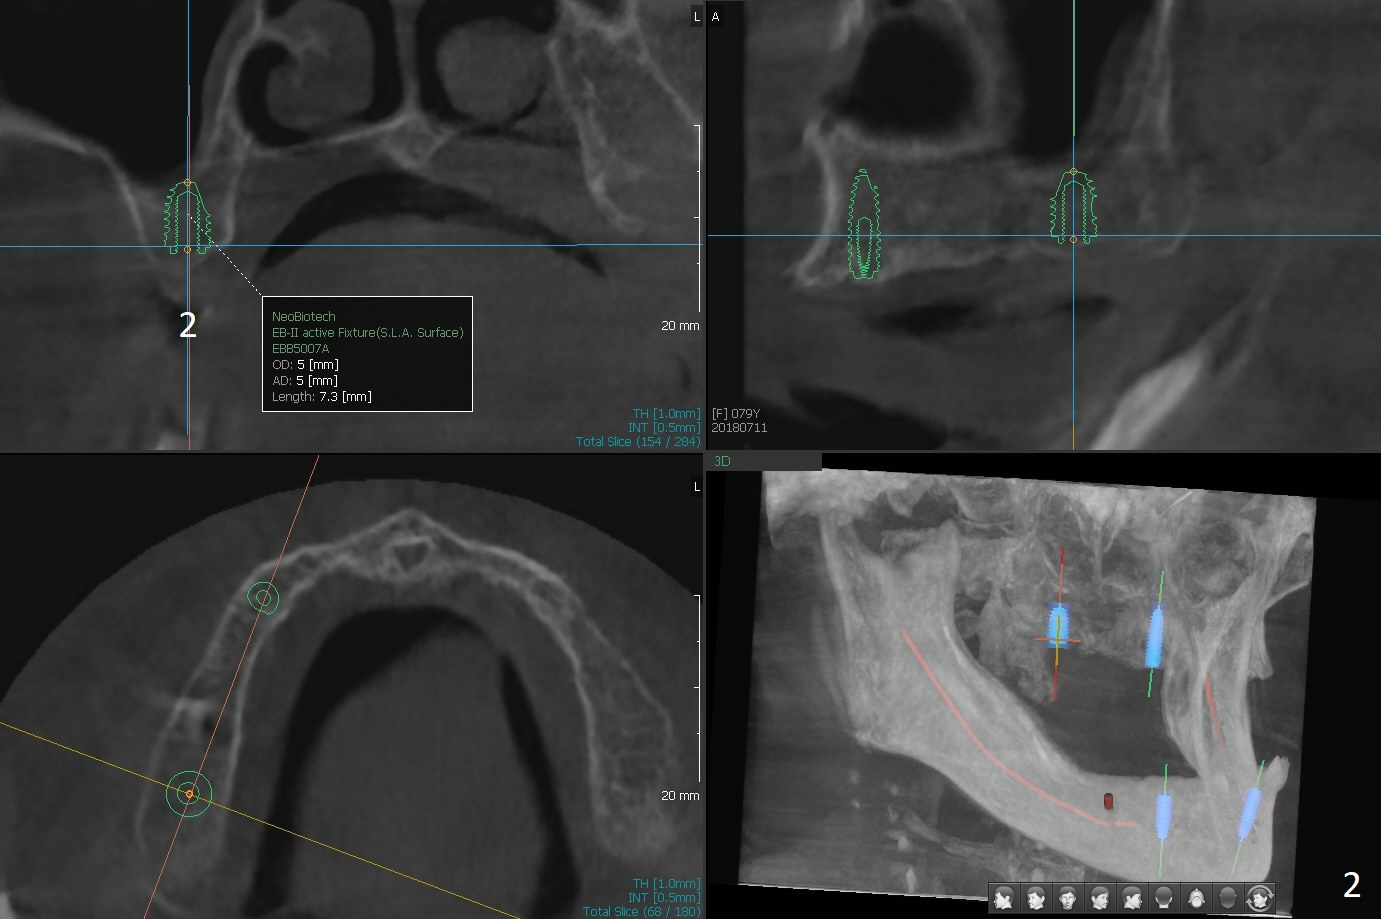

A 80-year-old woman wants to correct cross bite of complete dentures (Class II relationship). It seems that implant supported overdentures can make it possible (retention). Six implants will be placed in the maxillary canine and 2nd premolar and 2nd molar areas with surgical guide (Fig.1-6 (anterior ridge narrow)). Bone density is low. Prepare soft reline.